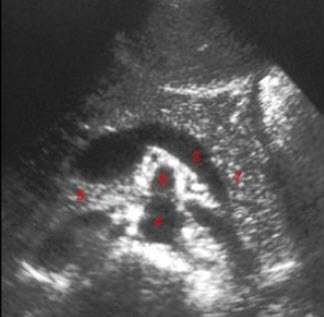

54、单项选择题

某患者左室长轴切面超声心动图如图所示,诊断为()

A.正常声像图

B.主动脉瓣关闭不全

C.二尖瓣关闭不全

D.室间隔缺损

E.房间隔缺损